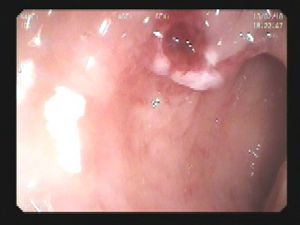

肠息肉 肠息肉切除状态

软组织夹保驾护航